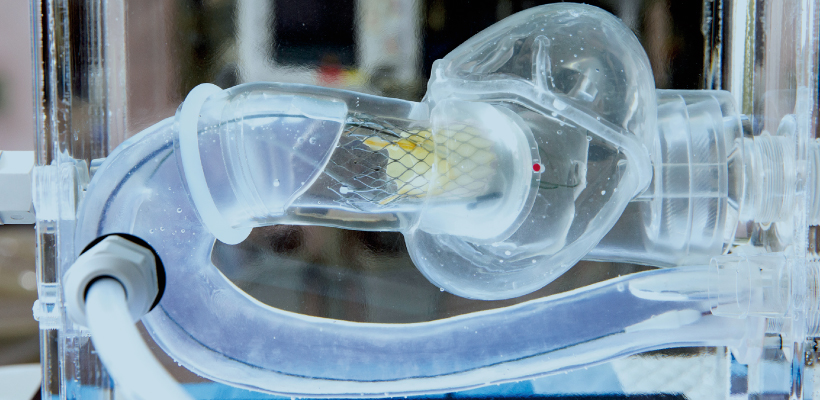

Vascular IVR

Products

- 3D printing